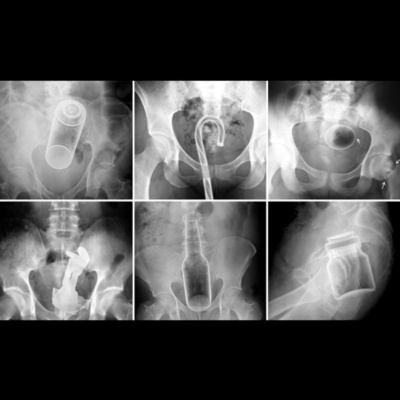

EMBARRASSING ER VISITS!!! Holy shit! Guys researching this was so gross! Lol! I picks the best ones I found and let me tell you, there may need to be a part two! Men do me a favor and be smarter with your man bits! Call/text my google voice number call/text 805-664-1828 and hear yourself on a podcast episode! I TRIED SOME SODA CAN TIKTOK HACKS https://youtu.be/8TuHmee6nM8 GOODBYE LOS ANGELES...HELLO ATLANTA https://youtu.be/wUMtFCr31Ec I DRANK A BOTTLE OF WATER IN UNDER 10 SECONDS!!! https://youtu.be/DTdS4RbsJEE ************************** Amber “Smiles” Jones PO BOX 533 Lovejoy, GA 30250 *************************** Podcast Twitter/IG:@itsprosilly Personal Twitter/IG:@trusmilesjones Email me: itsprofessionallysilly@gmail.com Be sure to SUBSCRIBE/FAVORITE/REVIEW❤️❤️❤️ CALL ME 805-664-1828 ~GET A PERSONALIZED SHOUTOUT TODAY ON CAMEO